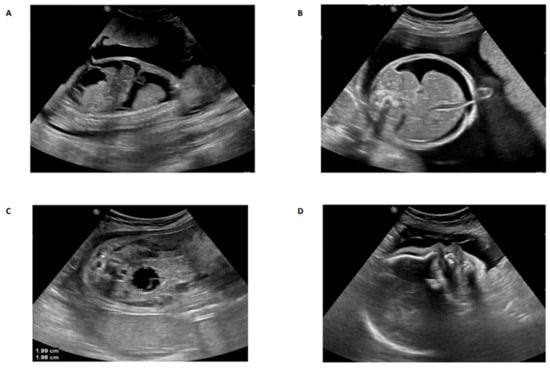

Fetal Anomalies Associated with Novel Pathogenic Variants in TMEM94

3. Results and Discussion